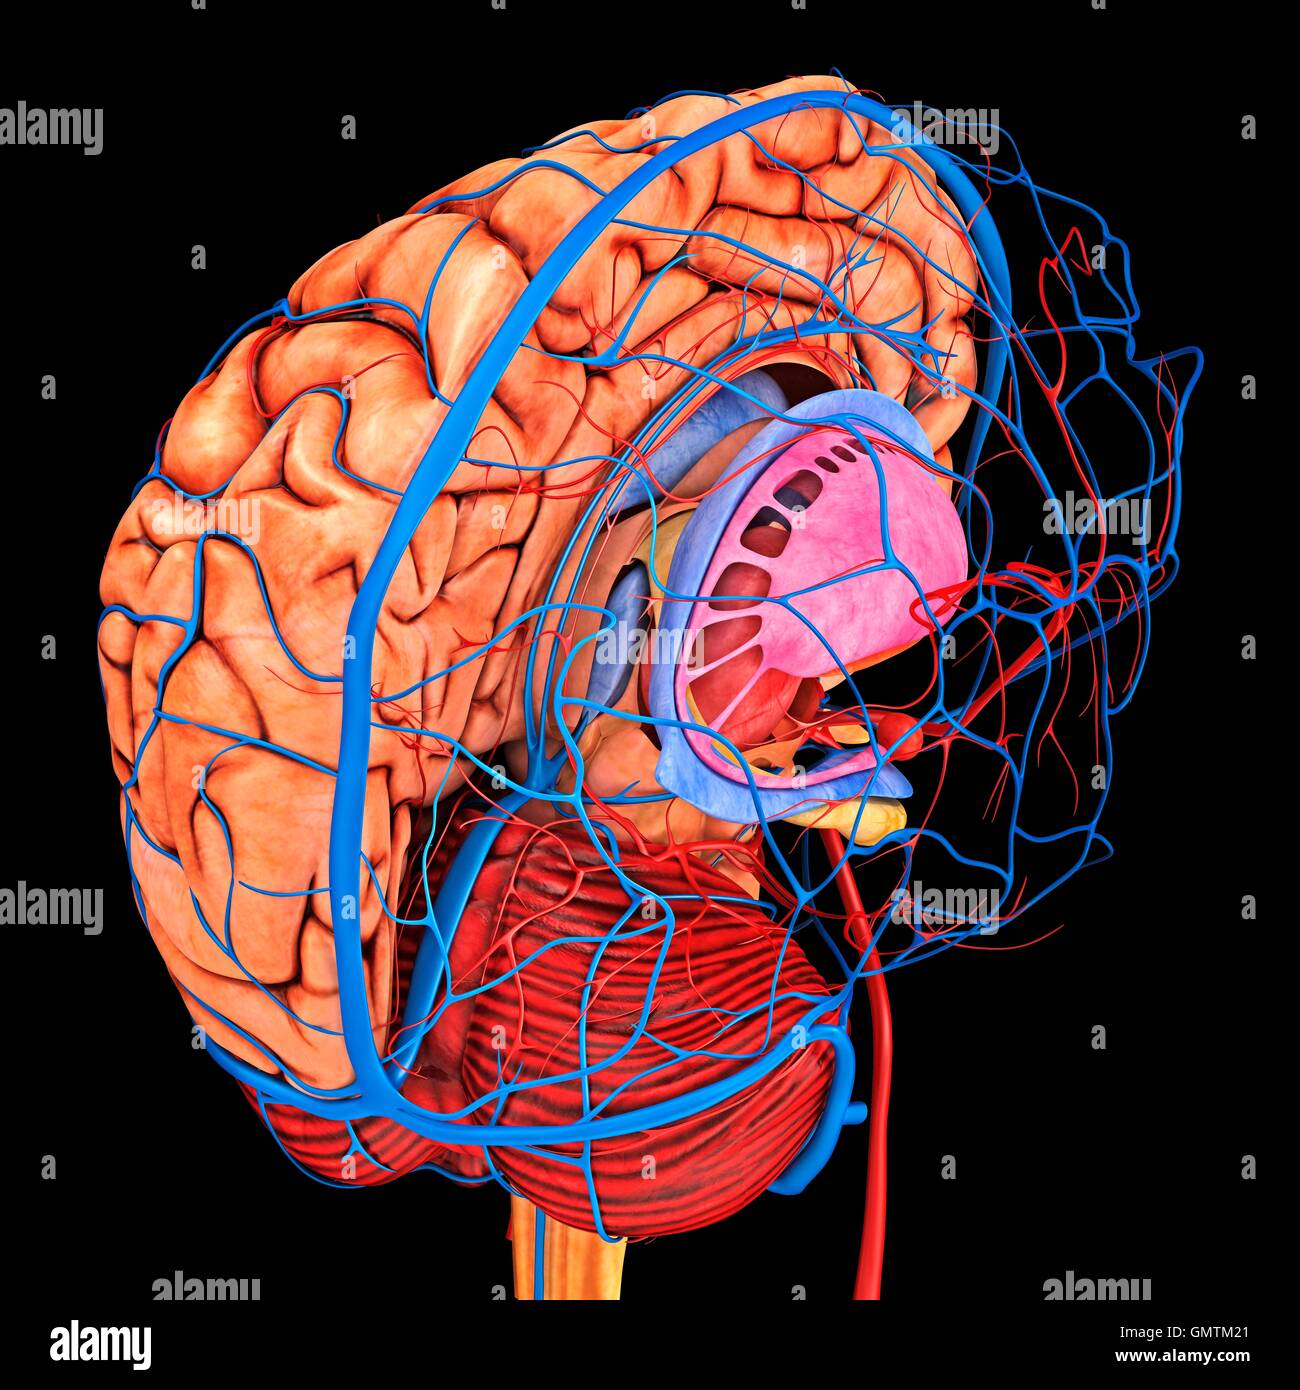

RFGMTM2D–Gehirn-System und Blut Gefäßversorgung. Grafik zeigt das Gehirn mit Arterien (rot) und Venen (blau).

RF2BTEMBH–Schematische Darstellung des menschlichen Kreislaufsystems, der Herzanatomie und der Gehirnblutversorgung

RFGMTM21–Gehirn-System und Blut Gefäßversorgung. Grafik zeigt das Gehirn mit den richtigen Großhirn entfernt und Arterien (rot) und Venen (blau).